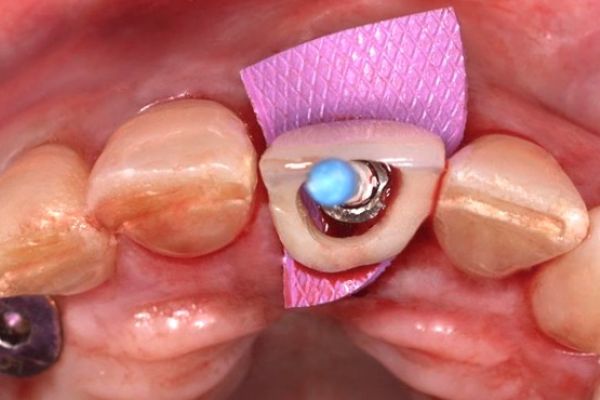

Finalmente, este número se completa con el caso clínico de Guerra de la Cruz y cols. centrado en la colocación de implantes postextracción con provisionalización inmediata en el sector estético, con un seguimiento de cuatro años. Este trabajo detalla la aplicación de protocolos actuales en implantología estética, destacando la importancia de la planificación y ejecución para lograr resultados funcionales y estables a largo plazo.